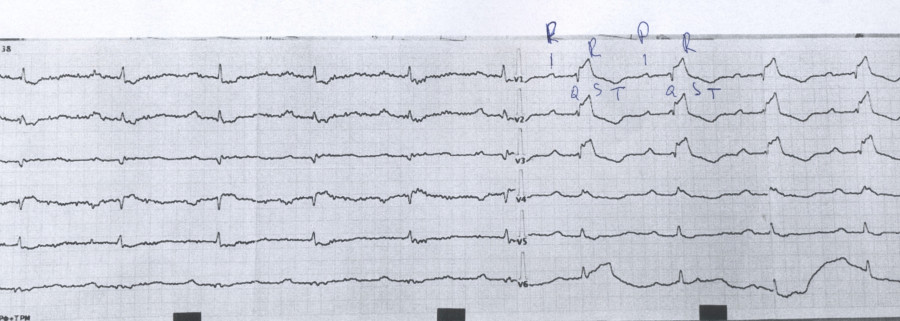

Это редкий врожденный порок сердца, при котором трехстворчатый клапан (раздел правое предсердие — правый желудочек) смещен вниз в полость правого желудочка. Это приводит к расширению правого предсердия, уменьшению полости правого желудочка и недостаточности клапана.

1fc6d2a5-83f9-4123-9f73-4cc010a287db.jpg [ 134.84 KiB | Просмотров: 208 ]

Xw7WCr9tREGr8OM4-EObYk9cqa01tZc1jJofc_qWl4DkuE32nxvmZHV1A5WaDqS54yDVXkjiZnIrbrP-bZhiZ8nE.jpeg [ 1.45 MiB | Просмотров: 208 ]